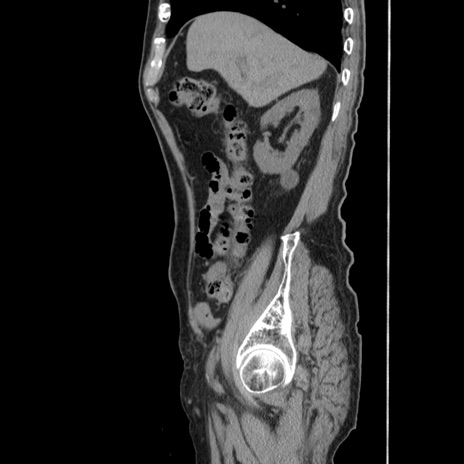

症例24(矢状断像)

【症例】80歳代男性

【主訴】左側腹部痛、嘔吐

【現病歴】本日早朝より左腹部に痛みあり。昼頃嘔吐認めたため、救急要請。

【既往歴】直腸癌(Mile手術)、胆摘

【身体所見】意識清明、BT 35.9℃、BP 221/93mmHg、SpO2 97%(RA) 、腹部:左ストーマ周囲に限局性の腹部膨隆あり。 膨隆部自発痛・圧痛あり・軟。